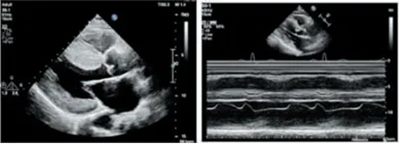

肥厚的左心室壁 二尖瓣运动曲线

左室流出道彩色血流

左室流出道血流速度